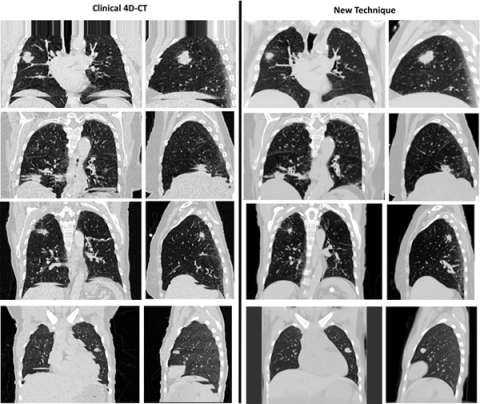

5DCT exploits standard fast helical acquisition with simultaneous breathing surrogate measurement, deformable image registration, and a breathing motion model to remove sorting artifacts. The accuracy of the motion model is assessed by reconstructing the original fast helical scans, which provide a ground truth.

breathing

Figure 2. (Left column) Examples of clinical 4DCT images. (Right column) Sorting artifact-free image generated using the 5D technique.